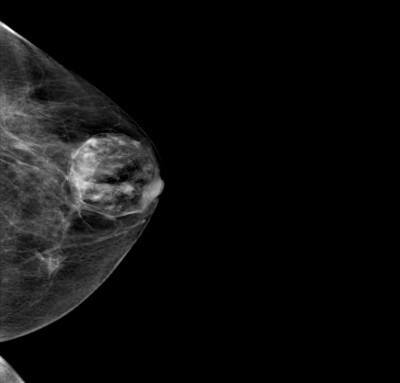

👉They are round, oval, or lobulated and are usually well-circumscribed.

👉They have a mixture of water density and fatty elements and frequently have either a capsule or the appearance of a capsule resulting from surrounding compressed breast tissue.

👉A mammographically classic hamartoma does not require further imaging, short interval follow-up, or biopsy.